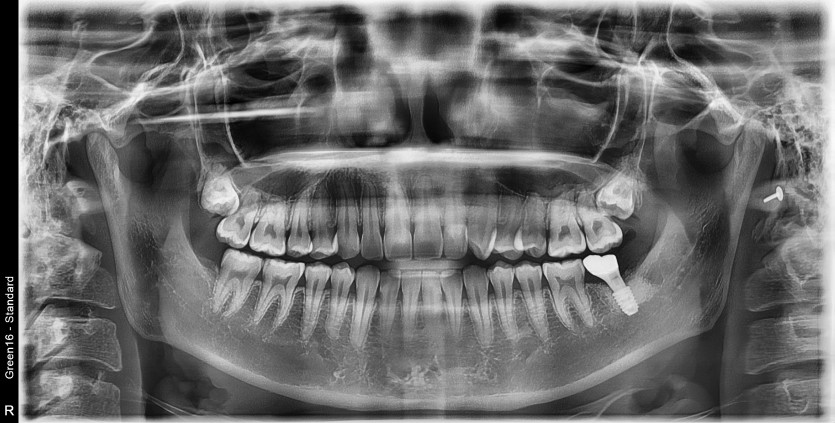

#38 사랑니 발치

구강 외과 전문의가 당일 발치 했습니다.